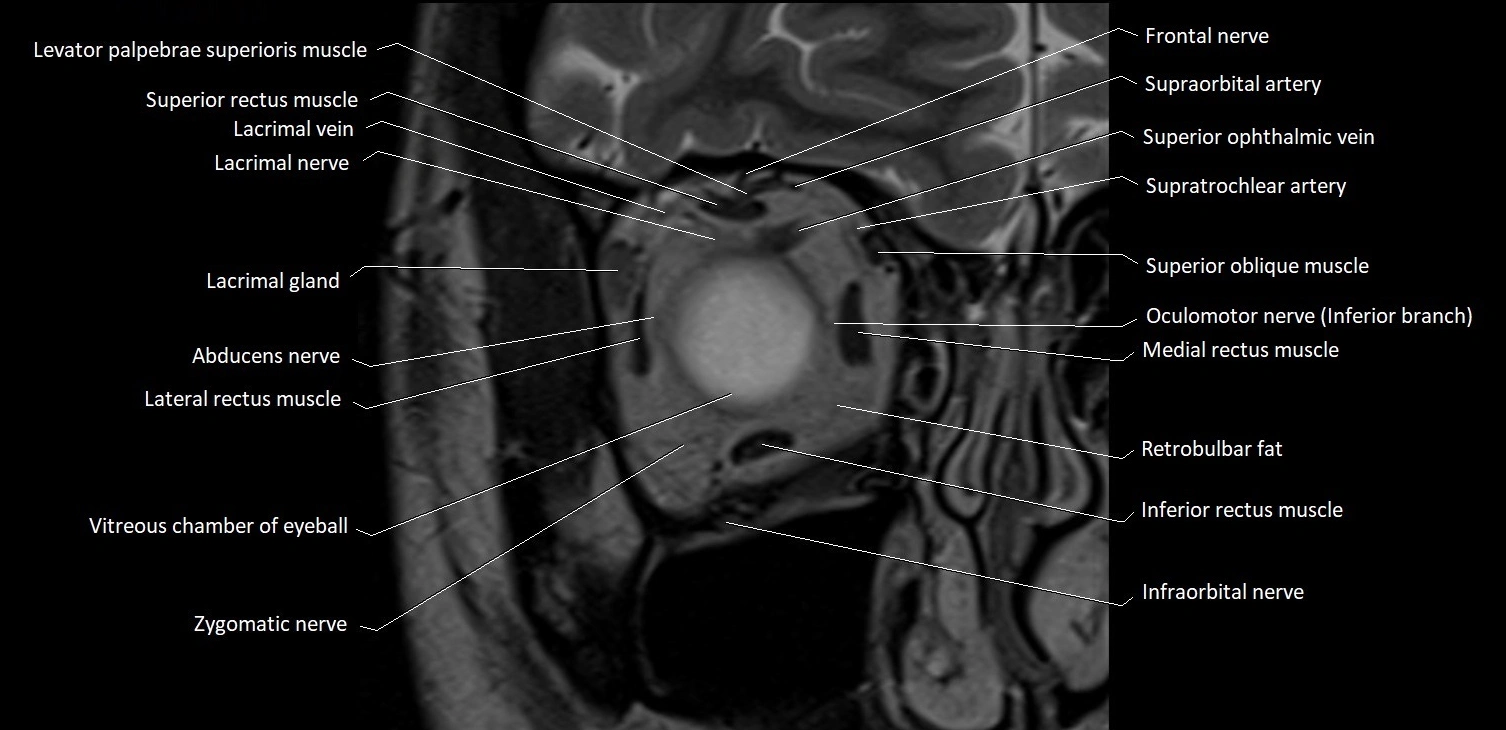

- Abducens nerve (Cranial nerve VI)

- Abducens nerve (orbital part )

- Lateral rectus muscle

- Inferior rectus muscle

- Medial rectus muscle

- Superior oblique muscle

- Superior rectus muscle

- Retrobulbar fat

- Infraorbital nerve

- Zygomatic nerve

- Lacrimal gland

- Lacrimal nerve

- Lacrimal vein

- Superior ophthalmic vein

- Supratrochlear artery

- Supraorbital artery

- Frontal nerve

- Oculomotor nerve (inferior branch)

- Vitreous chamber of eyeball